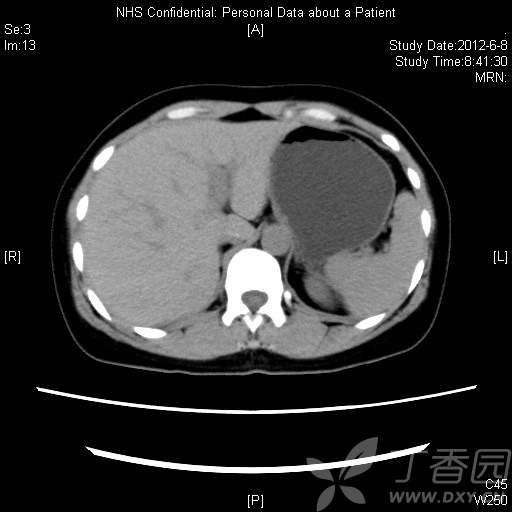

CT资料:

img